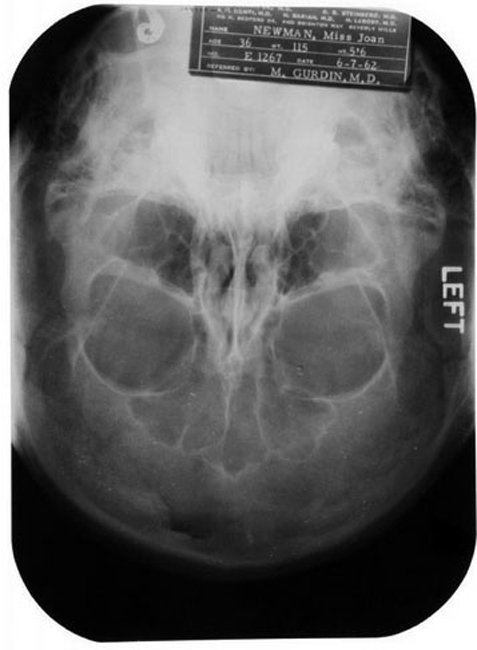

Στην τιμή των 25.600 δολαρίων πουλήθηκε ο ιατρικός φάκελος της Μέριλιν Μονρό, σε δημοπρασία που οργάνωσε ο οίκος Julien’s στο Σαββατοκύριακο στην Καλιφόρνια. Η δημοπρασία συγκέντρωνε προσωπικά αντικείμενα πολλών σταρ του κινηματογράφου καθώς και άλλων προσωπικοτήτων, όπως της Νταϊάνα, της Ελίζαμπεθ Τέιλορ και της Τζούλι Άντριους. Ωστόσο, στο επίκεντρο του ενδιαφέροντος πολλών αγοραστών βρισκόταν ο ιατρικός φάκελος της Μέριλιν, που αποδεικνύει ότι η χολιγουντιανή σταρ είχε υποβληθεί σε πολλές αισθητικές επεμβάσεις σε νεαρή ηλικία.

Ο φάκελος περιείχε πολλές ακτινογραφίες του προσώπου της αλλά και λεπτομέρειες των επεμβάσεων στις οποίες είχε υποβληθεί. Ενδεικτικά, αποκάλυπτε ότι η μεγάλη σταρ είχε κάνει πλαστική στο πηγούνι και στην άκρη της μύτης της το 1950, σε ηλικία 24 ετών, ενώ το 1957 είχε μία εξωμήτρια κύηση.